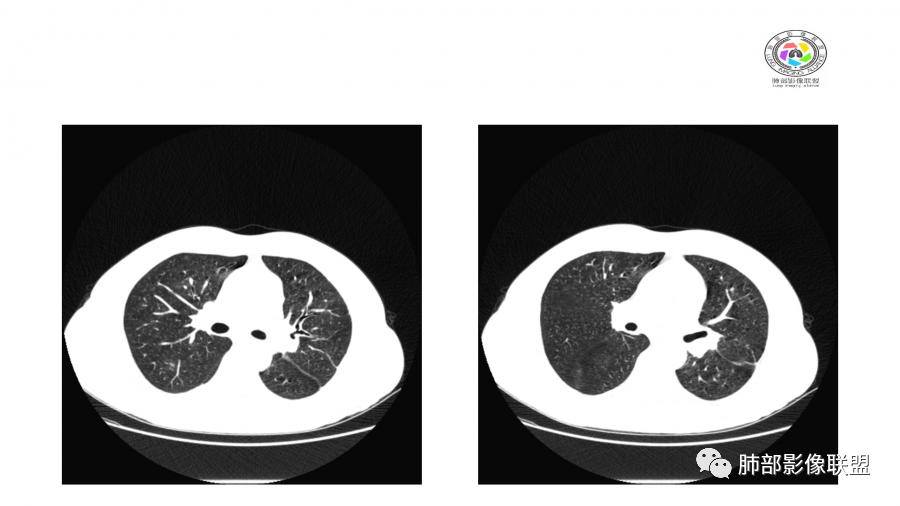

中年男性,高血压,肾功能衰竭,贫血病史,尿潜血阳性。3.8双肺野多发斑片磨玻璃实变影,结节影,边缘模糊,周围有晕征,内见支气管充气征,主要沿支气管血管束分布,部分胸膜下分布,3.12号病灶有吸收好转,4.8号斑片实变影基本吸收,主要沿支气管血管束分布结节影,边缘平直收缩,4.28病灶大部分吸收好转,双肺支气管血管束增粗,有少量结节影。考虑ANCA相关性血管炎可能性大,第一次片子觉得隐球菌不排除,但是后面没有抗真菌治疗就吸收了,觉得隐球菌可能性不大。

10天后:病灶继续吸收好转

伴随少量胸水

应该与气道无关

符合间质、血管来源病变

此起彼伏

有肾功能不全

支持与肾病相关

警惕血管炎